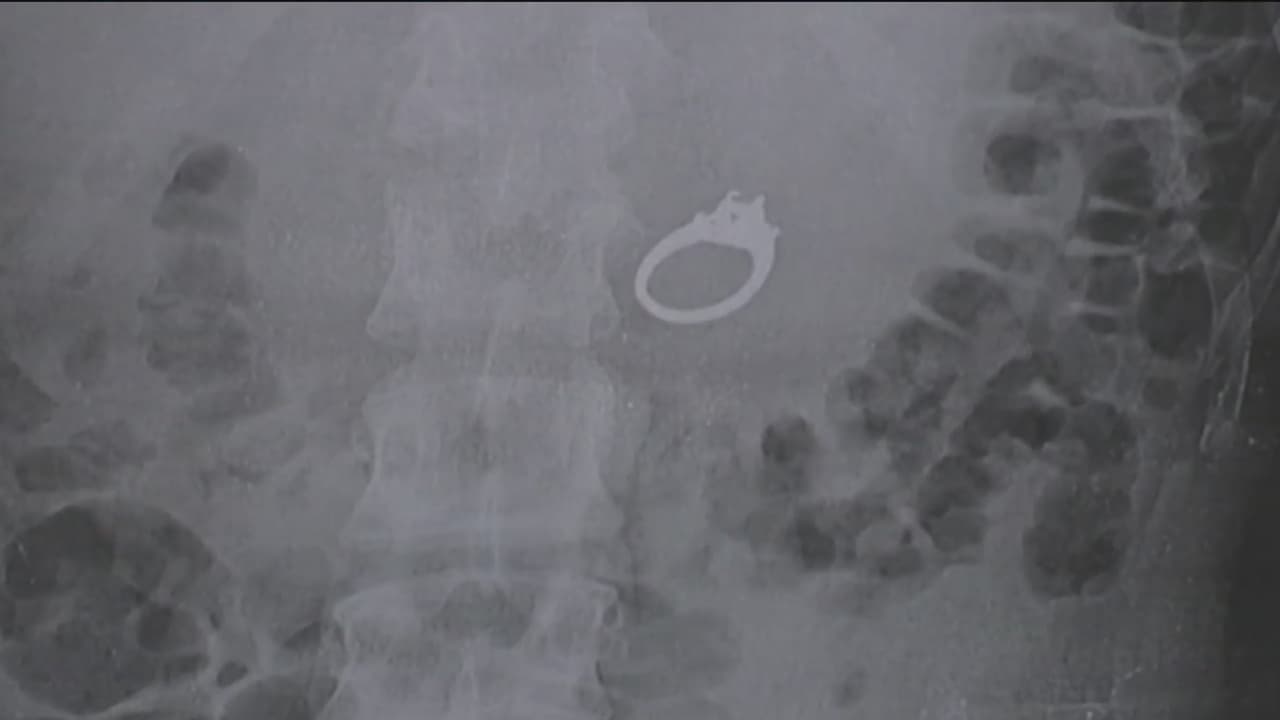

Mujer en California se traga su anillo de compromiso mientras dormía

Jenna Evans soñó que iba en un tren y su novio le pidió que se tragara el anillo de compromiso, mientras él enfrentaba a un grupo de delincuentes. Te contamos cómo terminó todo.